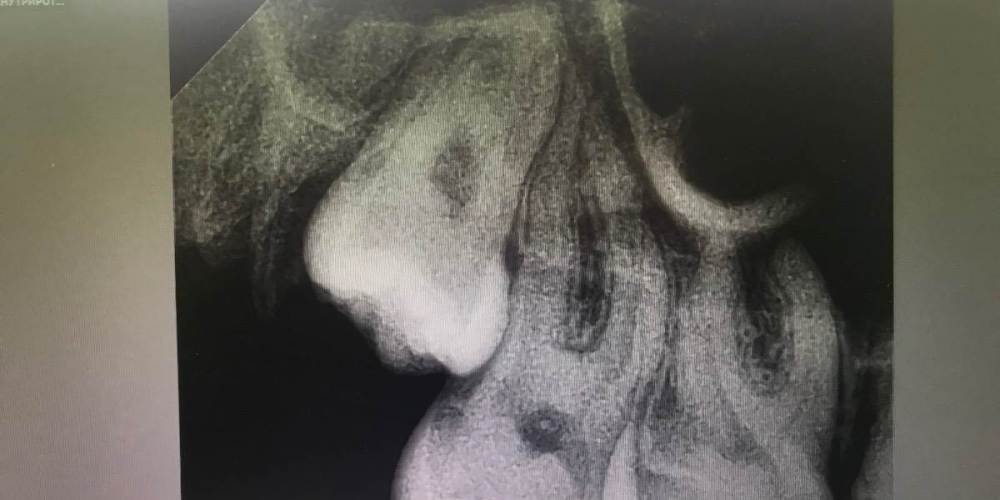

cryptiik Опубликовано 16 февраля, 2023 Поделиться Опубликовано 16 февраля, 2023 Расшифруйте, пожалуйста, снимки 16 и 17 зубов. Ссылка на комментарий

annda Опубликовано 16 февраля, 2023 Поделиться Опубликовано 16 февраля, 2023 Для точной оценки глубины и расположения полостей нужны прикусные снимки.А для диагноза -жалобы и объективные данные,а не вот эта абстракция. 1 Ссылка на комментарий